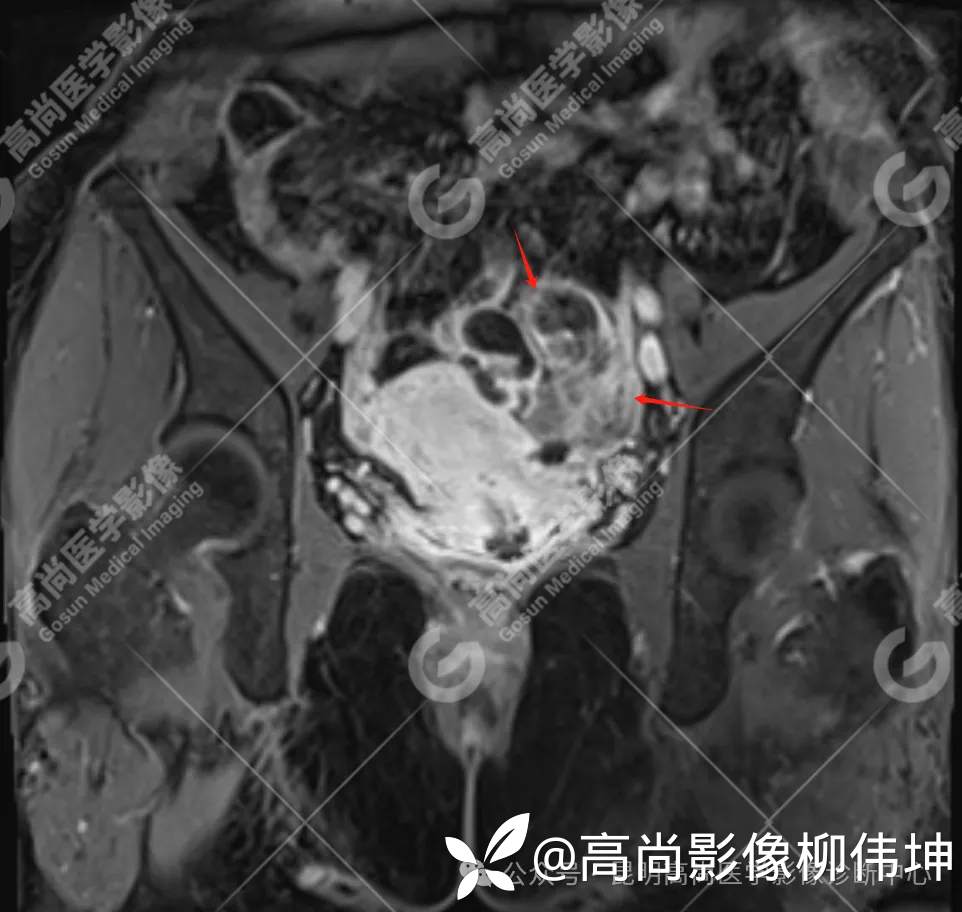

T2WI-cor

(2)MRI表现:通常双侧发生,体积巨大,呈外生性、囊实性、乳头状生长,其内见大量长T1长T2液性信号影及线性分隔,囊壁厚薄不均,可见壁结节及不同比例实性成分,呈T1等信号,T2略高信号。扩散受限,DWI呈高信号,ADC呈低信号。增强扫描实性成明显强化。另外,常可检出腹水、腹膜增厚、盆壁及盆腔脏器受累、淋巴结肿大等表现。